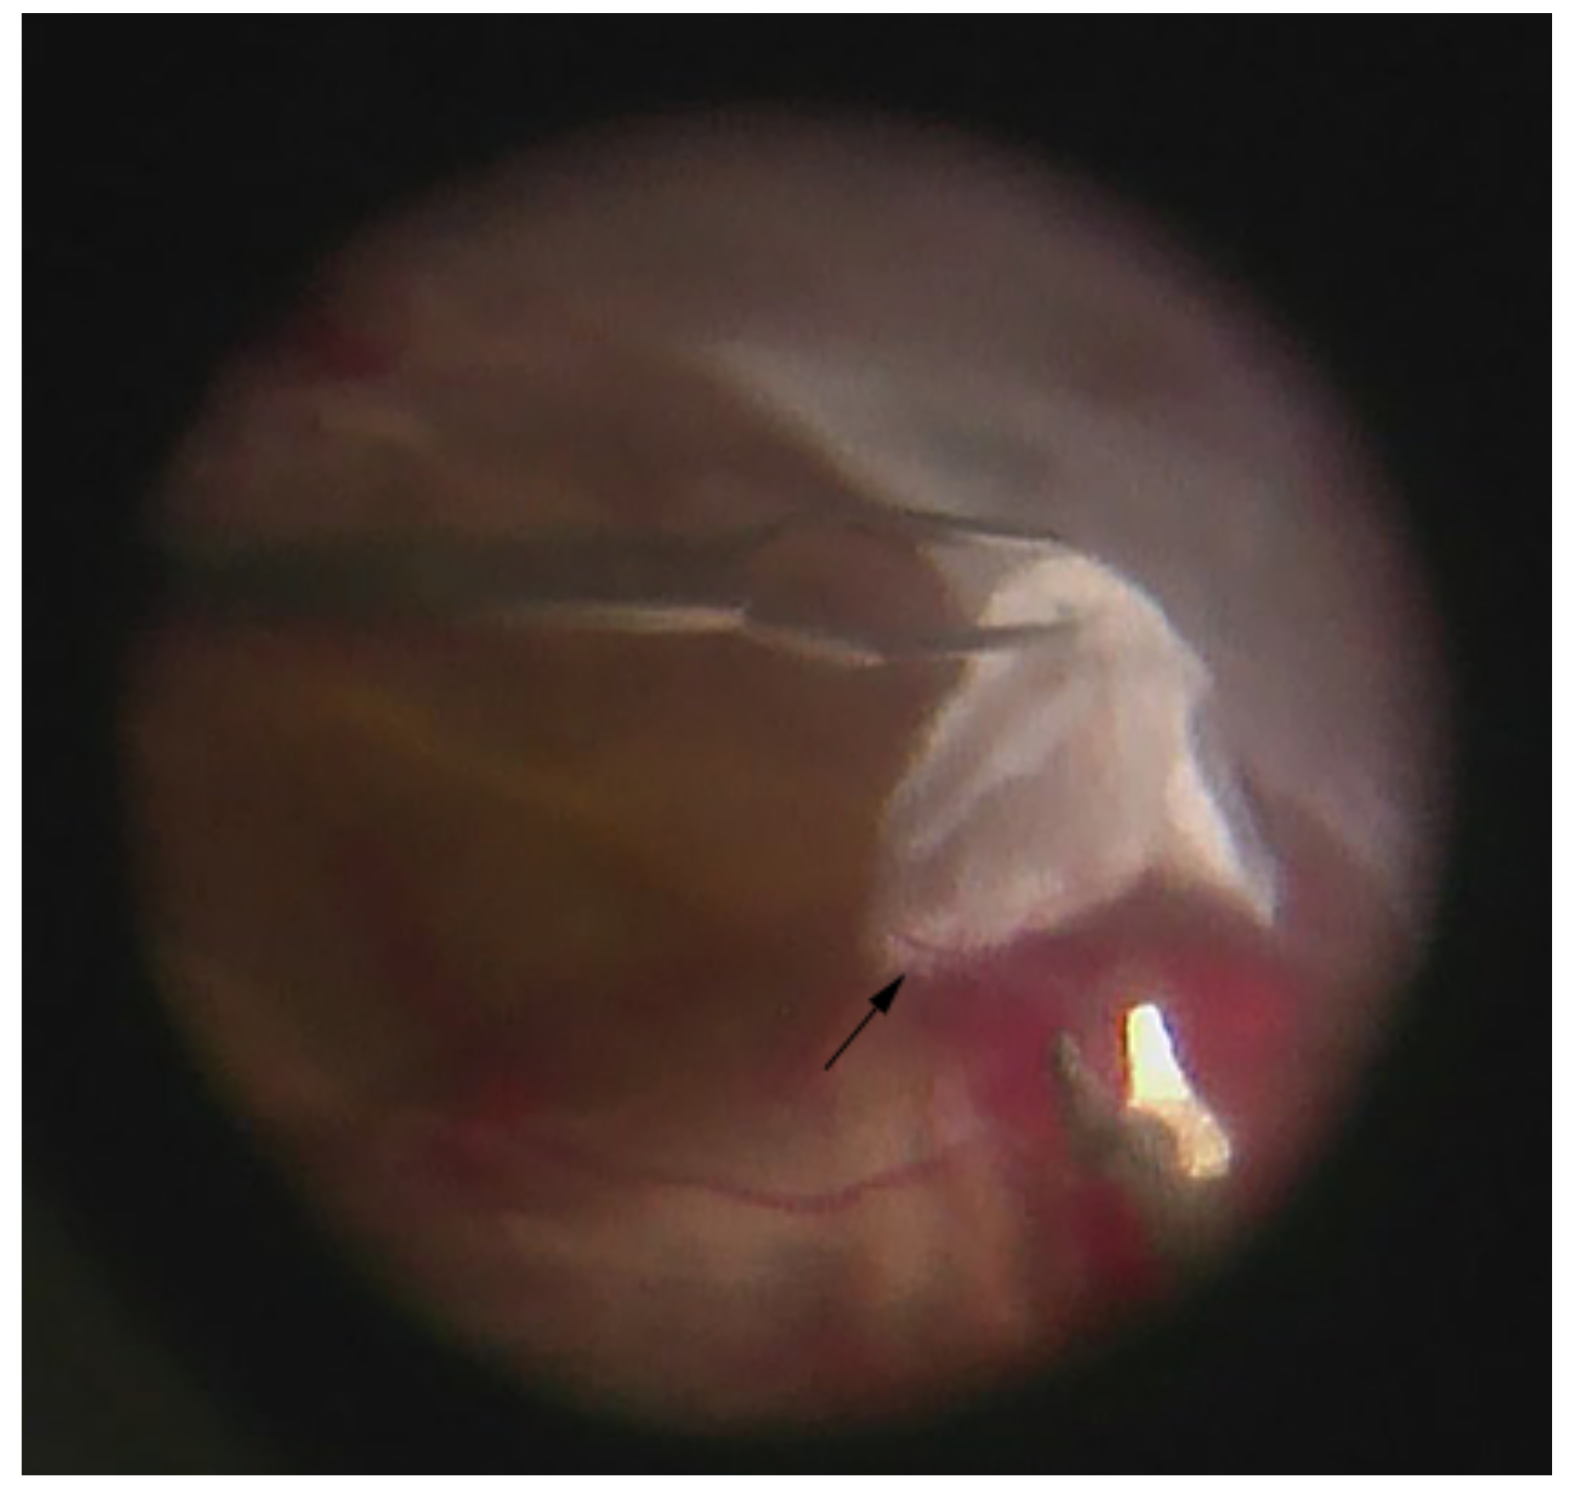

2.2. Human Vitreous Sampling Technique